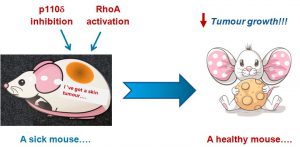

Τίτλος Ερευνητικού Έργου: Διερευνώντας μία συνδυασμένη αντίθετη στόχευση της RhoA και της p110d PI3K ως μία καινοτόμο προσέγγιση για τη θεραπεία του καρκίνου του δέρματος

Επιστημονική Υπεύθυνη: Παπακωσταντή Ευαγγελία